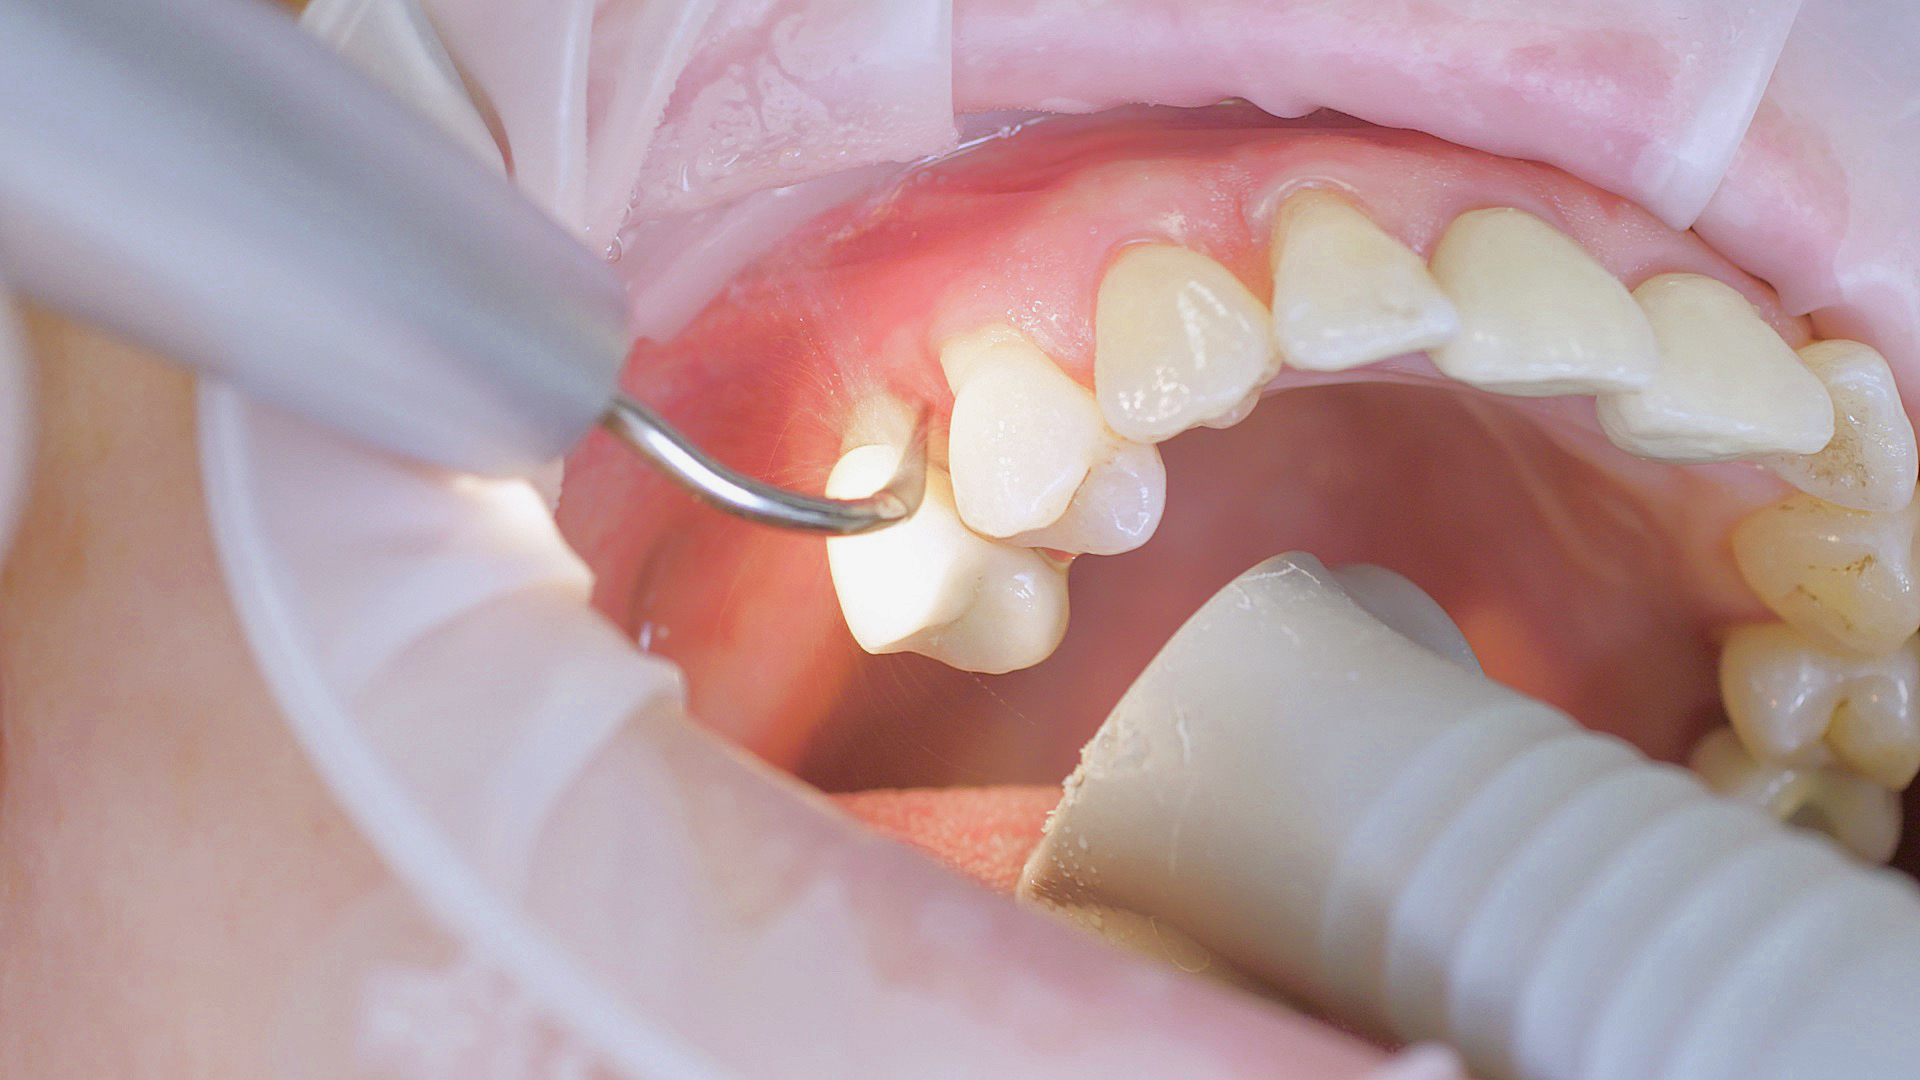

Where necessary, initial periodontal treatment is carried out. First, professional tooth cleaning establishes healthy gingival conditions. In this procedure, calculus (Fig. 1) and biofilm (Fig. 2) are removed as far as the gingival sulcus. In combination with careful instruction on oral hygiene, this gives the patient the basis for long-term freedom from inflammation.15

Calculus removal using an ultrasound

Fig. 1: Calculus removal using an ultrasound (W&H Tigon+ with a 3U tip) is a key part of professional tooth cleaning.